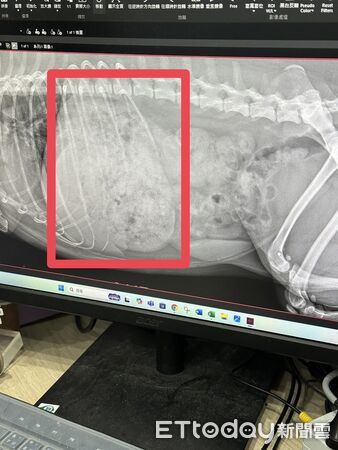

事後Cyanna把碰糖帶去找獸醫,X光照下肚子裡滿滿都是食物,不幸中的大幸是牠沒有吃到乾燥劑,「有輸點滴,開了口服膠囊,目前體重已來到7.9公斤」,之後飼主表示以後會多注意家裡的食物收納,避免意外再度發生,網友也紛紛留言表示,「椪糖要改名變椪轟了」、「小心胰臟炎,太油了」、「狗:是虎爺附身」。

▲肚子裡滿滿都是食物。(圖/Threads@icexanna提供,請勿隨意翻拍,以免侵權。)